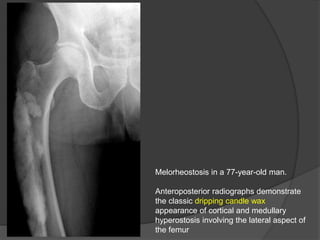

Melorheostosis (Leri disease) is a type of mixed sclerosing bone dysplasia,

with disturbances in both endochondral and intramembranous ossification.

The disorder is sporadic and typically manifests in late childhood or early

adulthood.

Characteristic radiographic appearance consisting of cortical and medullary

hyperostosis of a single bone or multiple adjacent bones with a flowing

“dripping candle wax” appearance.

The skeletal lesions may progress throughout life, with the lower extremities

being more commonly affected than the upper extremities.

The skeletal abnormalities, as well as the extraosseous involvement, typically

Melorheostosis in a 77-year-old man.

Anteroposterior radiographs demonstrate

the classic dripping candle wax

appearance of cortical and medullary

hyperostosis involving the lateral aspect of

the femur